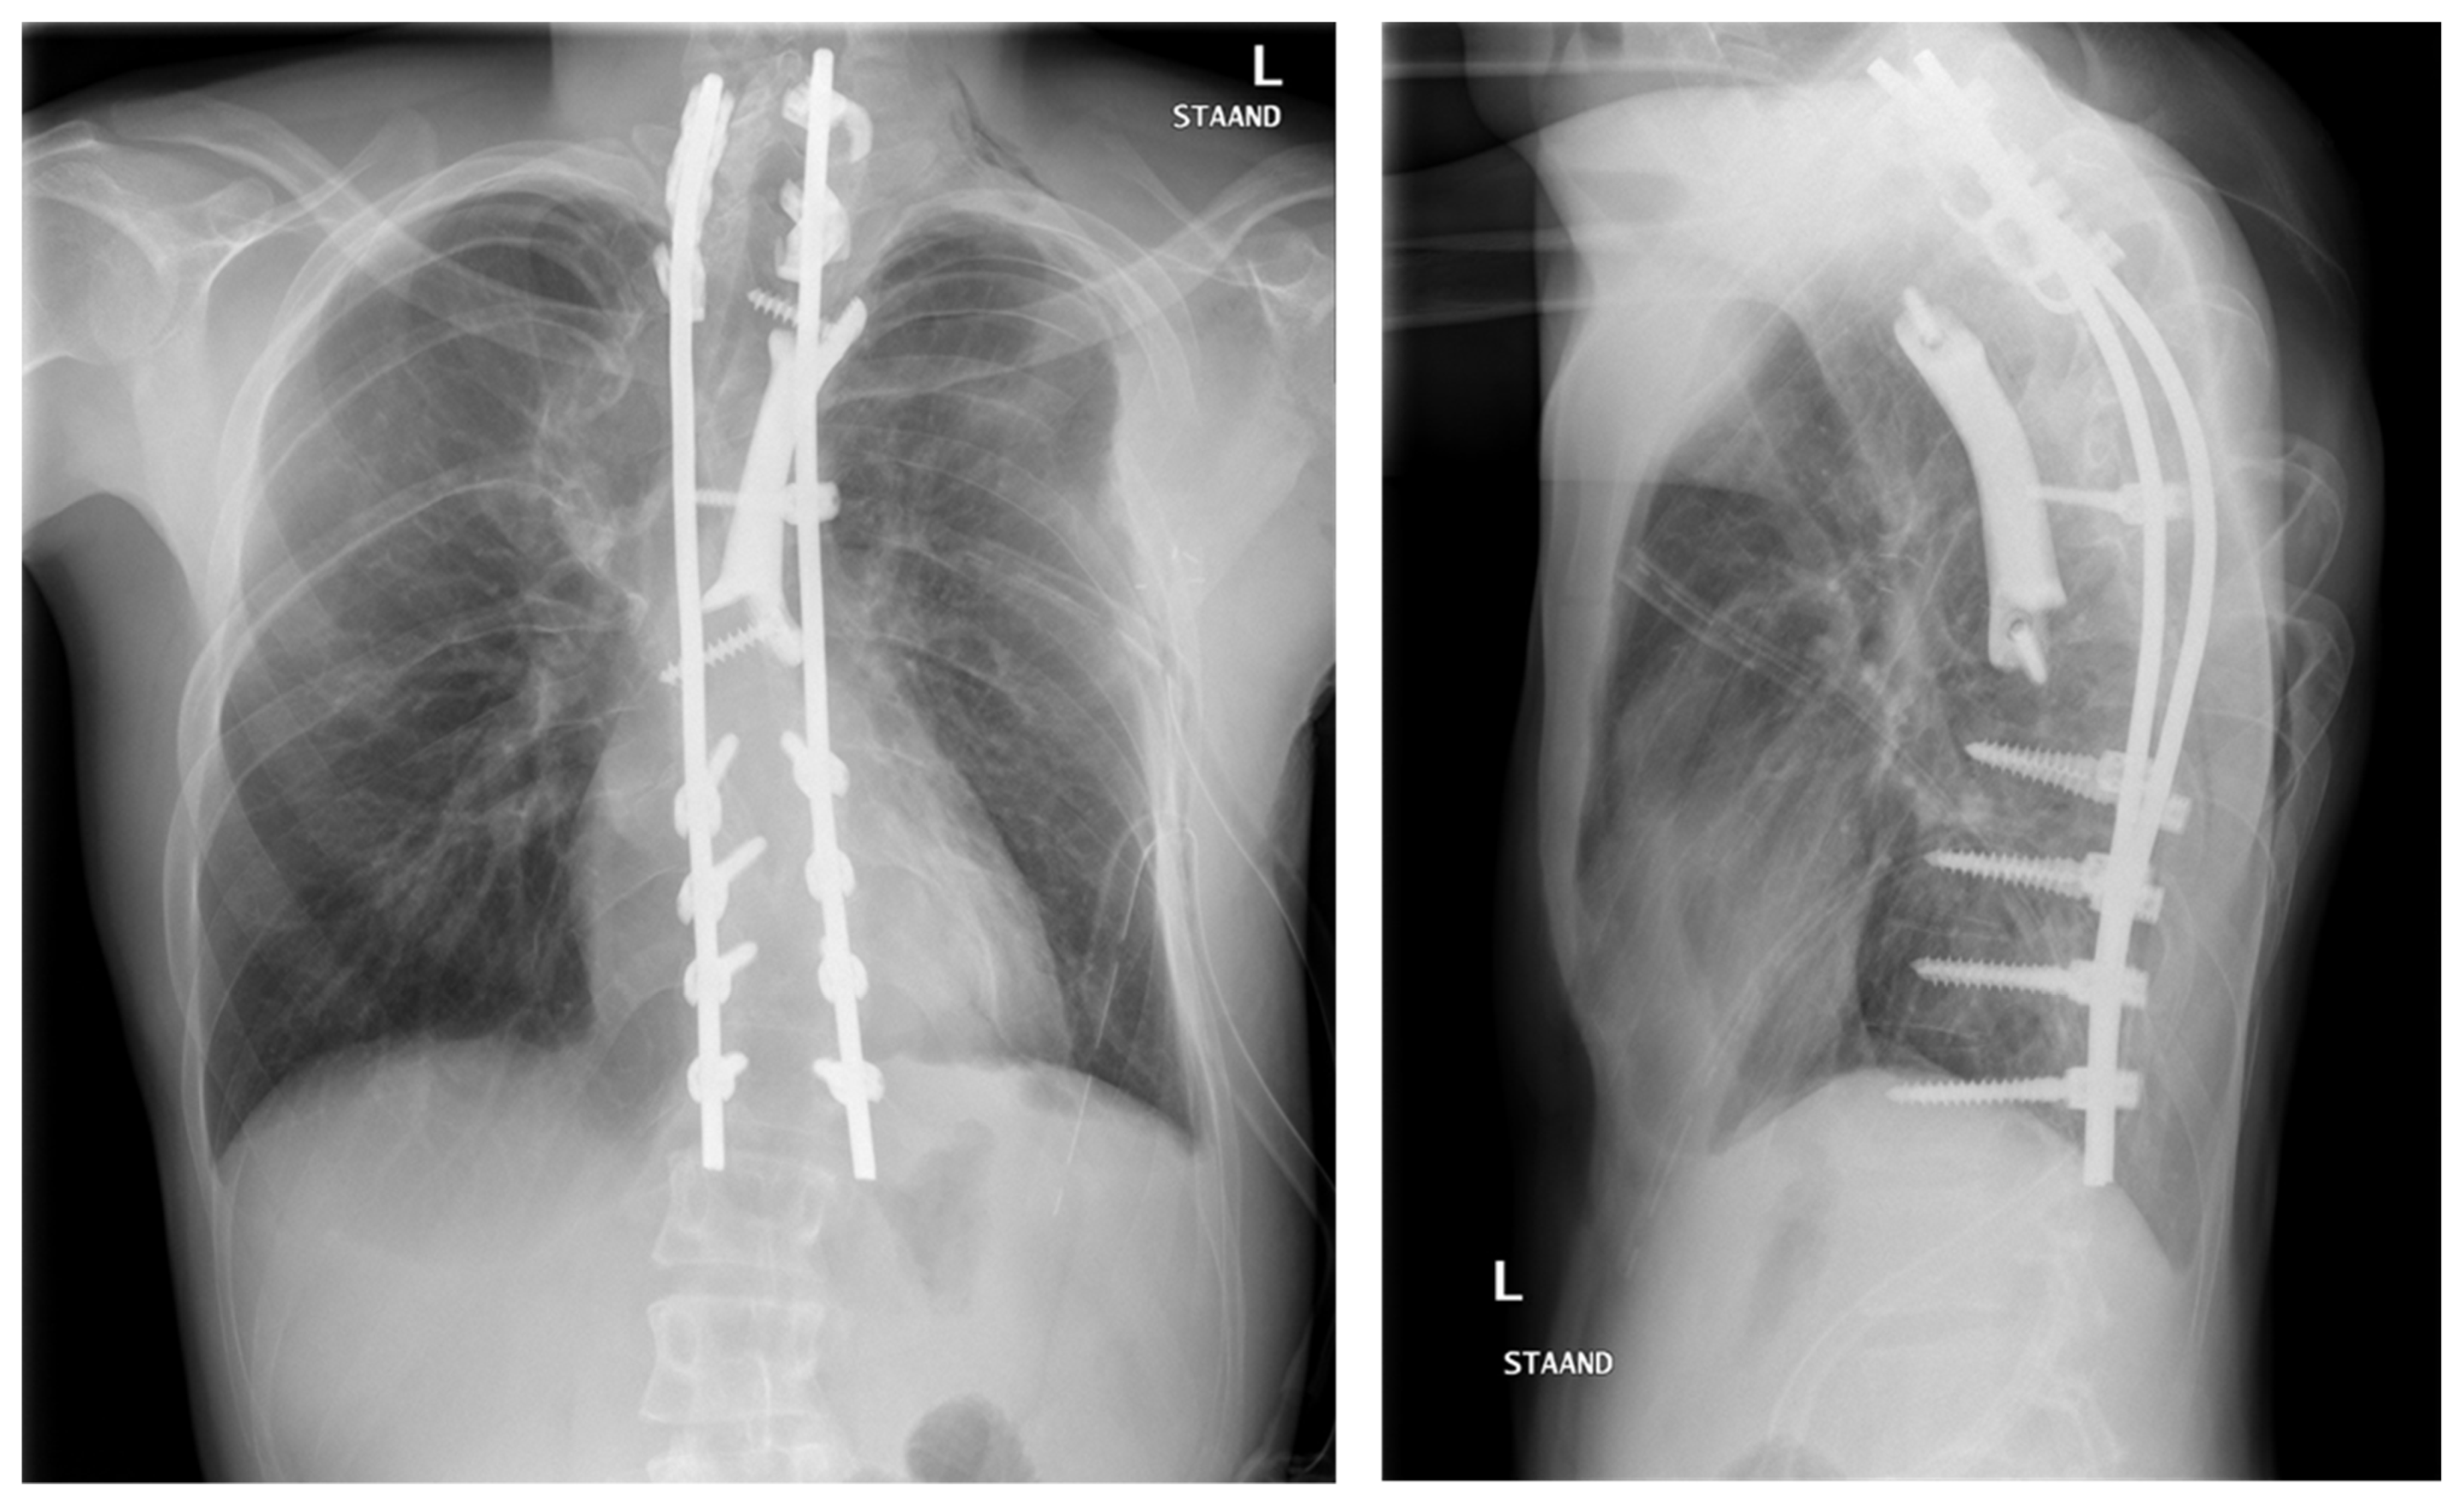

6.3. Clinical Experience with Spinal Prosthesis